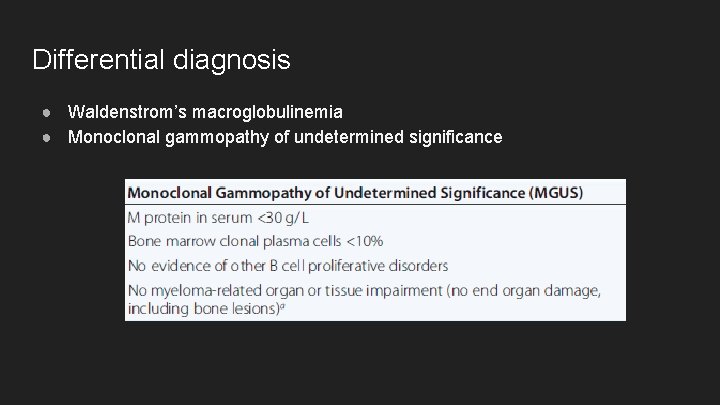

Differential diagnosis ● Waldenstrom’s macroglobulinemia ● Monoclonal gammopathy of undetermined significance